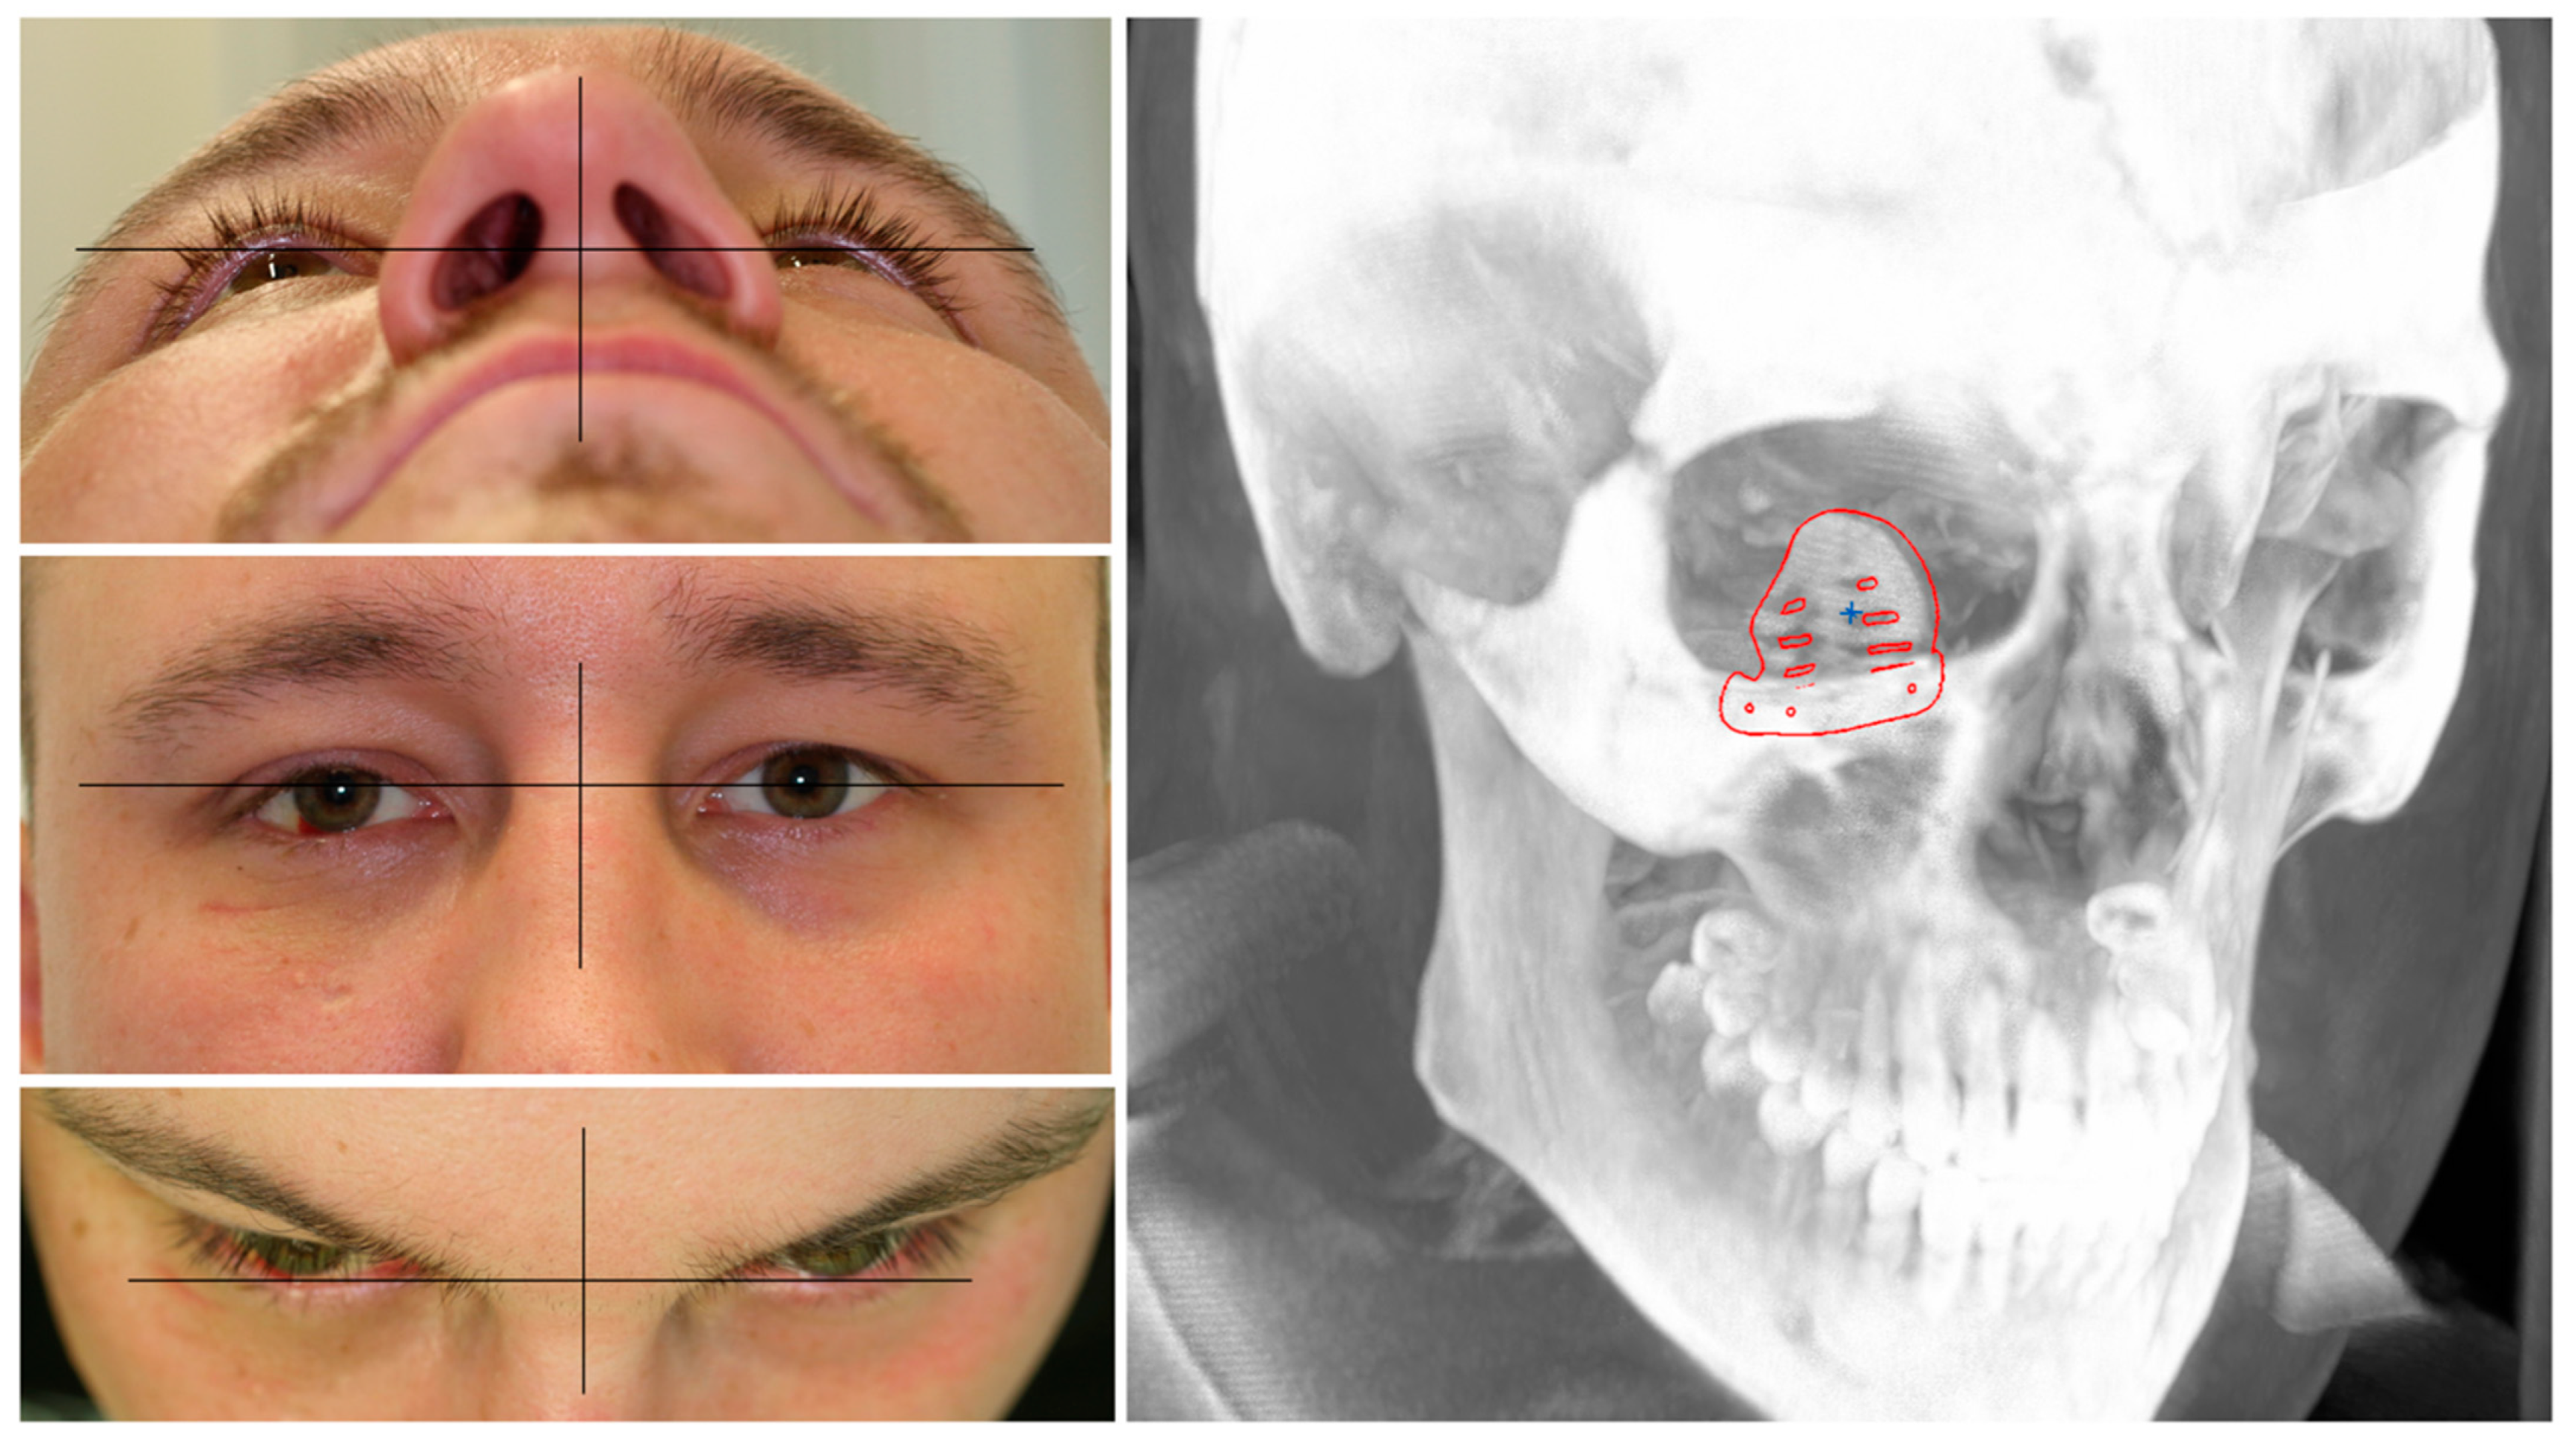

A patient with an orbital floor fracture due to a fall was in need of primary orbital reconstruction. He suffered from binocular double-vision, hypesthesia of the right infraorbital nerve, and a hypoglobe with slight enophthalmos on the affected right side (see Figure 1). The CT data showed a defect size of 17.9 mm in the coronal plane and 23.4 mm in the sagittal plane. Due to the defect size, the mode of reconstruction was chosen as an alloplastic reconstruction with a titanium mesh. To show the different fitting qualities, a pre-fabricated titanium mesh was compared to a PSI.

Figure 1.

Clinical photographs of the patient showing an enophthalmos in the perspective from below and above, with a hypoglobe present on the right affected side as visible in the frontal view. The coronal and sagittal planes of the pre-operative CT scan displaying the traumatic defect of the orbital floor on the right side.